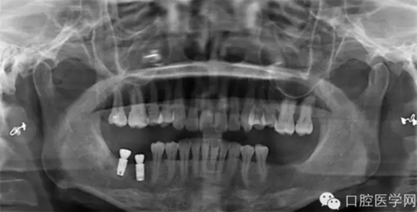

第四種,韓國(guó)奧齒泰種植體